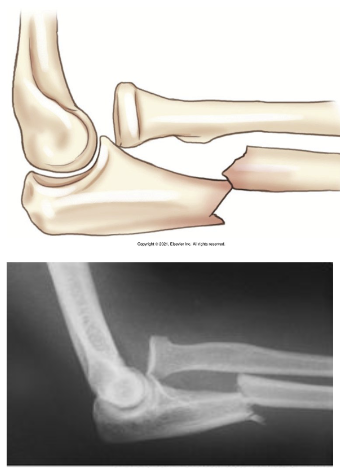

What type of fracture is this?

Monteggia

What is a monteggia fracture?

Fx of proximal half of ulna with dislocation of radial head

May happen if raise arms to block blows to the head